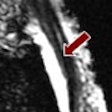

MRI points to ankylosing spondylitis anti-TNF response